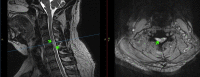

HOD 2 cervical MRI with and without contrast. Abnormal T2 hyperintense signals (green arrows) show segments of right-sided lesions between spinal cord levels C3–C6.